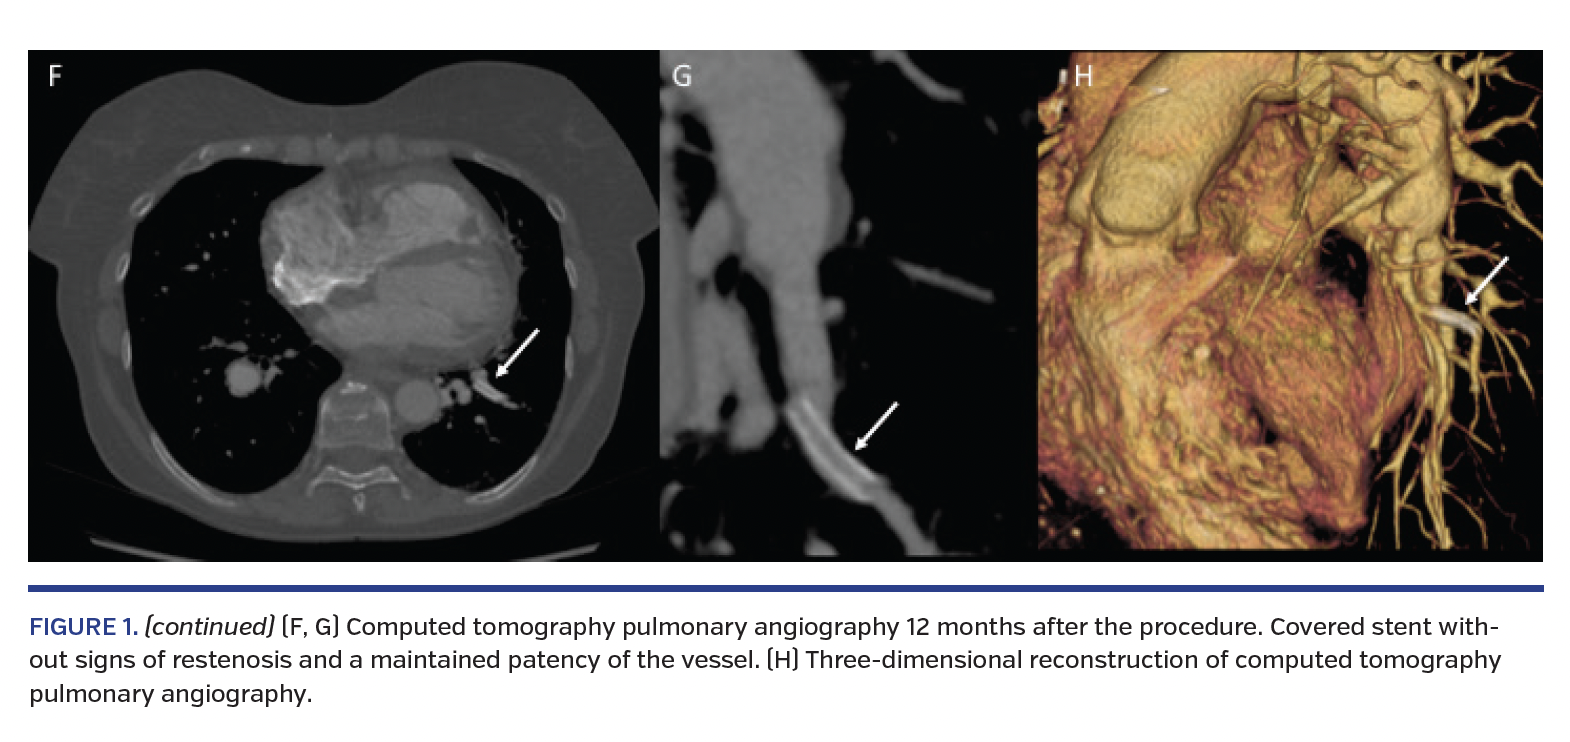

A 62-year-old female with residual pulmonary hypertension after pulmonary endarterectomy for chronic thromboembolic pulmonary hypertension (CTEPH) underwent balloon pulmonary angioplasty (BPA). At baseline, she was in functional class III and mean pulmonary artery pressure was 50 mm Hg. BPA was performed as a staged procedure; at the third BPA session, we targeted the left subsegmental A9a artery. Selective pulmonary angiography showed the ring-like lesion (Figure 1A). Subsequently, we dilated the lesion with a 5.0 x 20 mm Viatrac balloon (Abbott Vascular) (Figure 1B). However, immediately after deflation of the balloon, severe hemosputum and cough occurred. Pulmonary angiography showed extravasation of contrast medium (Figure 1C; Video 1) and pulmonary artery rupture and dissection were recognized. A 3.0 x 20 mm Jostent GraftMaster covered stent (Abbott Vascular) was implanted to the rupture site (Figure 1D). Control angiography revealed the disappearance of extravasation of contrast medium (Figure 1E; Video 2). Pulmonary computed tomography angiography performed 12 months later showed no signs of in-stent restenosis and patency of the vessel (Figures 1F, 1G). Three-dimensional reconstruction of the computed tomography pulmonary angiography is shown in Figure 1H.

The ring-like lesions in CTEPH patients are sometimes difficult to dilate because they are hard and fibrotic. For this reason, slightly oversized balloons are used. However, this may result in an increased risk of vessel rupture. Implantation of a covered stent not only protects the ruptured vessel, but also maintains perfusion in the future.